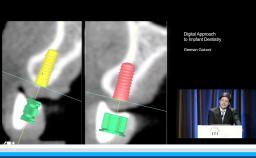

The congress lecture will discuss two techniques for sinus floor elevation (SFE) in implant dentistry: the lateral window technique and the transalveolar technique. Choice of method depends on anatomical considerations such as residual bone. Both methods show high implant survival rates, comparable to native bone (around 95%). Transalveolar SFE is suited for cases with enough residual bone and a flat sinus floor, but risks Schneiderian membrane perforation due to incomplete osteotomy. Advances in surgical instruments, including drills with safety ends and controlled hydraulic pressure, have reduced perforation risks in transalveolar SFE. However, for severely resorbed ridges or the presence of septa, the lateral window technique is preferred. The lecture will cover how to select the appropriate technique for each patient.

- outline how to achieve the controlled erosion of the sinus floor during the transalveolar technique